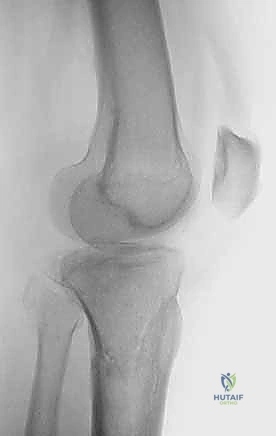

2. التصوير الإشعاعي (X-rays)

الخطوة الأولى هي التقاط صور أشعة سينية من عدة زوايا (أمامية خلفية، وجانبية). تعطي الأشعة السينية فكرة عامة عن وجود الكسر وموقعه، لكنها غير كافية لتقييم الكسور ثنائية اللقمة المعقدة.